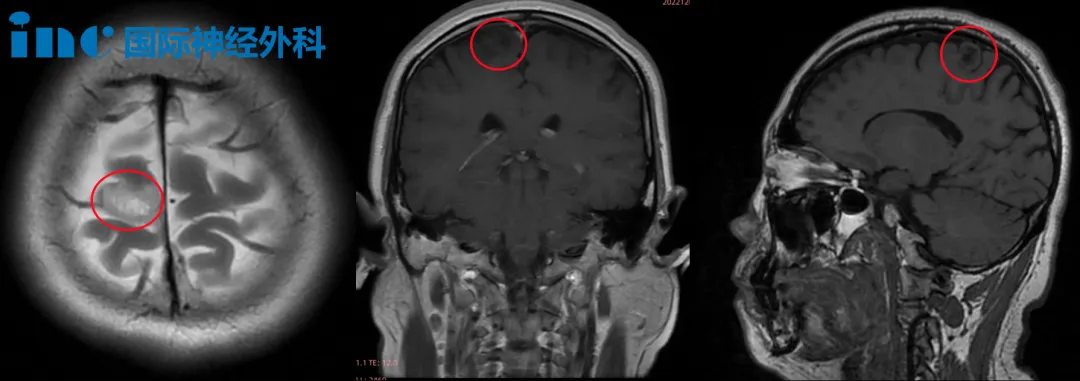

那天我在办公室突然癫痫发作,抽搐、晕倒,被紧急送医。检查结果出来:右额叶低级胶质瘤。

“额叶”,医生解释说,“是管认知、情绪和运动协调的高级‘指挥部’。”而我的瘤子,就长在运动功能区旁边。随着肿瘤的生长,一旦压迫到主运动功能区,很可能导致运动功能障碍。

从咨询到手术,我只用了不到一个月。2022年12月4日,巴教授在苏州为我主刀,肿瘤被完全切除。

起初在当地的医院也是做了一系列的检查,检查以后,当地医院的医生建议保守治疗。他们坦率地告诉我,肿瘤紧邻运动功能区,如果开刀,最大的风险是瘫痪致残。那段时间,我真的觉得看不到未来。

术后一年邮件随访评估中巴教授也表示:“低级别胶质瘤被完全切除,我们没有发现任何残余,附近的大脑结构和浅静脉是完整的。“